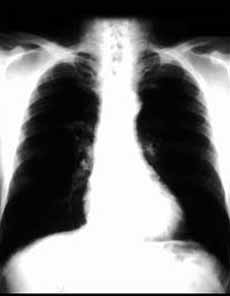

沙雷菌肺炎體徵

沙雷菌肺炎2.體徵雙肺可聞及乾濕性囉音,當肺葉或肺段出現實變時,可有相應肺段、肺葉的語顫增強,叩濁、可聞及支氣管呼吸音。危重病人可能有呼吸急促、發紺及休克等。